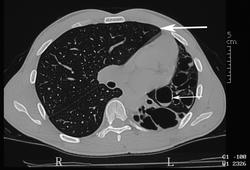

На компьютерных томограммах в заднемедиальном отделе нижней доли левого легкого виден участок повышенной воздушности, легочный рисунок в нем деформирован, не прослеживаются просветы сегментарных бронхов, нет дренирующего бронха.

"Секвестрированный" участок в заднемедиальном отделе нижней доли левого легкого кровоснабжается аномальной артерией, отходящей от аорты.